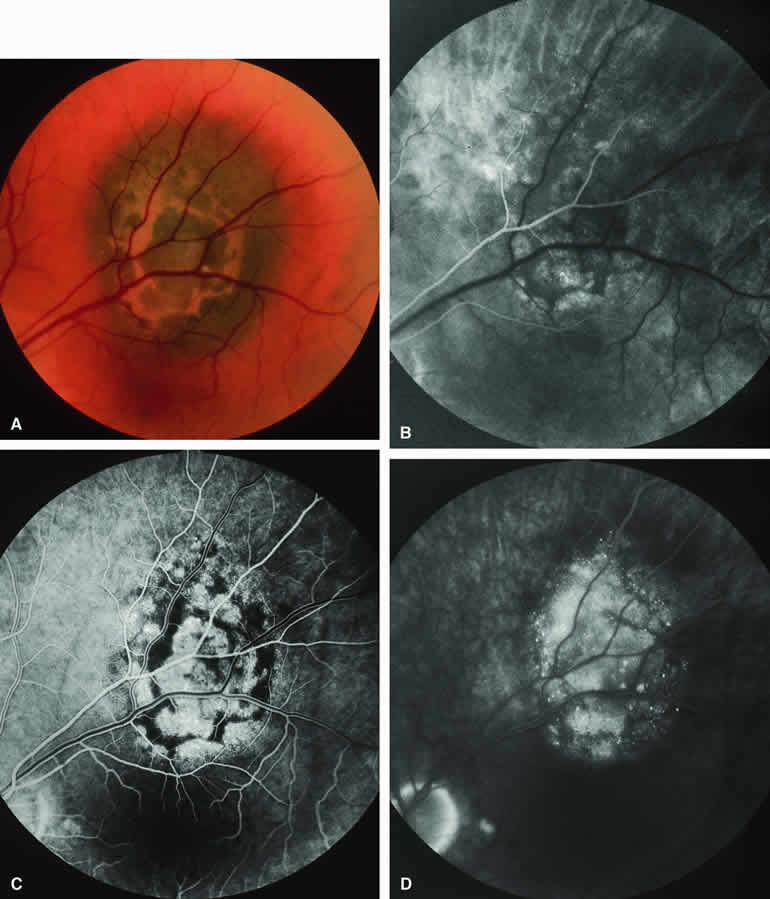

ICG angiography of a typical melanotic choroidal nevus (see Fig. 2) shows better definition of the basal area of the lesion than does fluorescein angiography. The entire lesion appears completely and uniformly dark throughout the ICG angiogram. Only the larger retinal blood vessels overlying the nevus are usually demonstrated on ICG angiography.

Amelanotic Choroidal Nevus

Approximately 10% to 15% of choroidal nevi are largely or completely amelanotic clinically. Fluorescein and ICG angiography of an amelanotic choroidal nevus (see Fig. 3) tend to show less prominent hypofluorescence of the lesion than they do with darkly melanotic nevi. Because of the lack of intracellular melanin pigment within the nevus cells, some large-caliber choroidal blood vessels running through the nevus may be visible in the region of the mass (see Fig. 3B and C). These choroidal blood vessels are better defined by ICG angiography than by fluorescein angiography. Amelanotic choroidal nevi often appear mildly hyperfluorescent in late-phase frames (see Fig. 3D).